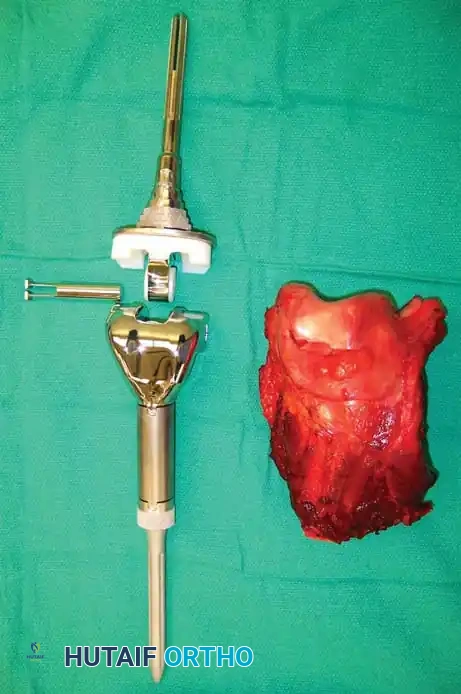

Image

Photograph of the resected distal femur specimen alongside the modular endoprosthetic implant prepared for reconstruction.

5. Reconstruction:

The femoral canal is reamed to accommodate the prosthetic stem. If using cement, a cement restrictor is placed, the canal is pulsatile lavaged, and PMMA bone cement is injected retrograde. The femoral component is impacted. The proximal tibia is then prepared with a standard tibial cut, and the tibial component is cemented into place. The rotating hinge mechanism is assembled.